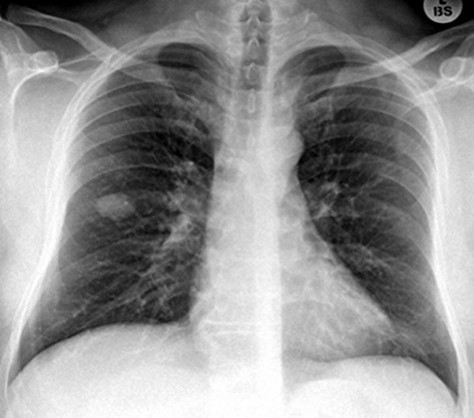

38yo male with dyspnea and pleuritic chest pain for a week

View: PA

DX: cavitary lesion associated with community acquired MRSA